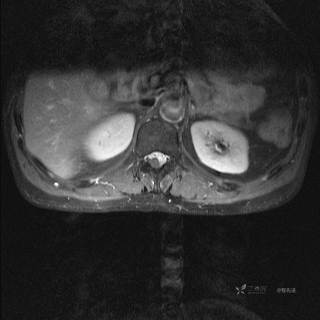

MR

T2

T2压脂

T1

T1增强

T1增强冠状位

T1增强横断位